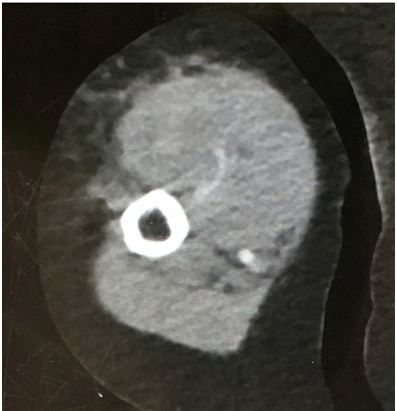

Patient History. An approximately 70-year-old woman with a history of atrial fibrillation presents to the emergency department with 3 hours of right biceps pain. There was no history of fever, heavy liftin, or injury. She does not know what medications she takes.

Examination. Vital signs were normal. Physical exam was normal except for swelling, firmness, tenderness, and slight ecchymosis to the right biceps area with no pain with passive stretch. Range of motion, sensation, and pulses were good.

Initial Concerns. Spontaneous bleed, compartment syndrome, biceps tendon rupture, infection, deep vein thrombosis

CT of the biceps is shown below.

CT scan, biceps